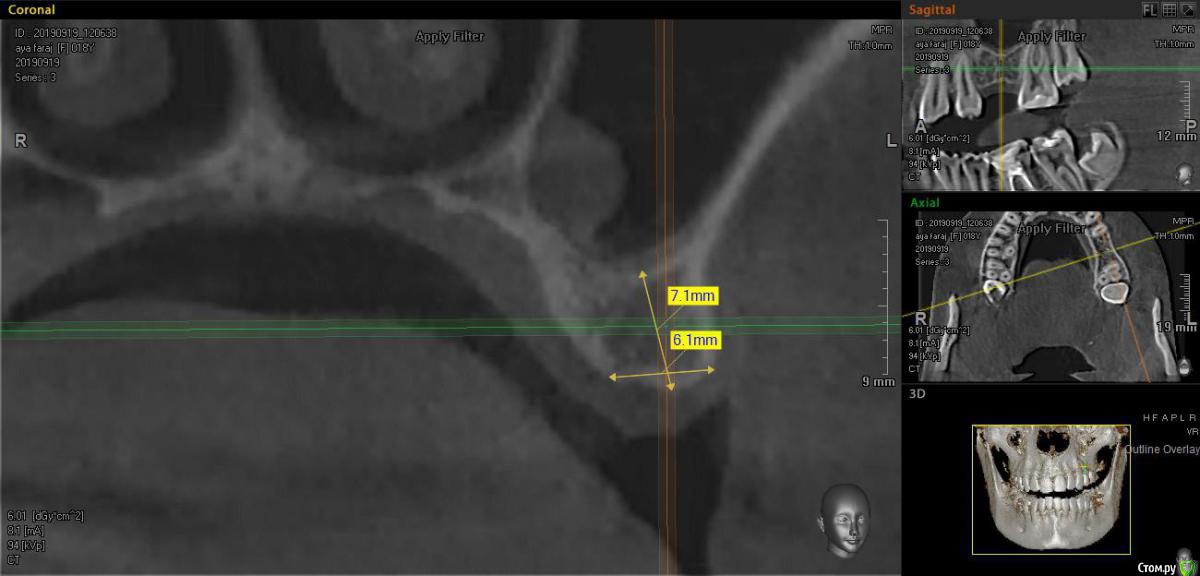

bilal Опубликовано 20 сентября, 2019 Поделиться Опубликовано 20 сентября, 2019 Хочу ставить straumann blt 4.1*10 с закрытым синусом..но на медиальной стенке полип или киста, является ли это противопоказанием? Или не замарачиватся и ставить 4.1*8 Ссылка на комментарий

bilal Опубликовано 22 сентября, 2019 Автор Поделиться Опубликовано 22 сентября, 2019 не войдет 4.8*8 ?ширина 6.1, нав лучше 4.1 будет Ссылка на комментарий

Дмитрий М Опубликовано 24 сентября, 2019 Поделиться Опубликовано 24 сентября, 2019 ширина 6.1, нав лучше 4.1 будетсудя по снимку, биотип слизистой - толстая, поэтому допустимо оставить меньше 1мм у шейки, хотя честно признаться, конкретно в данном случае сам бы наверное 4,1 выбрал бы Ссылка на комментарий

dr Alexandr Опубликовано 26 сентября, 2019 Поделиться Опубликовано 26 сентября, 2019 на мой взгляд, место хватает, полип не помеха ! если есть навык, можно спокойно заходить закрытым и импл 4.1/8 Ссылка на комментарий